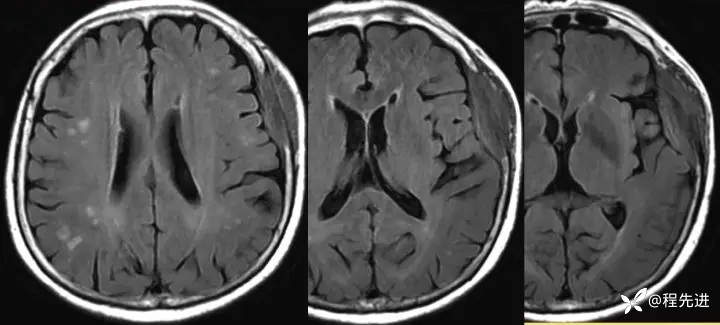

2年后:

img